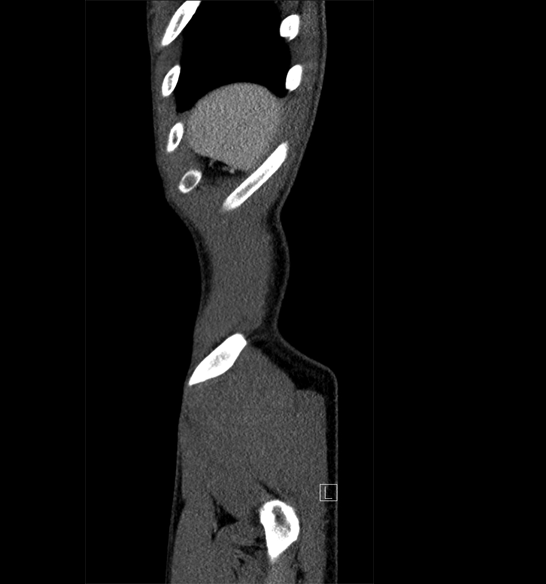

Body

Covers abdominal CT anatomy.